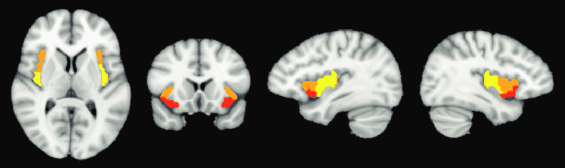

Klíčový objev: anterior insula

Moderní výzkum ukázal, že elektrická stimulace přední části ostrovního laloku (anterior insuly) umí extatickou auru navodit i u lidí bez epilepsie. Pacient, který nikdy předtím extázi nepocítil, popsal zážitek jako “nekonečnou propojenost” a “úplnou jistotu, že nic nemůže selhat”.

Zdroj: ResearchGate.net

Tři podoblasti pravé insuly identifikované pomocí klastrové analýzy ventrálního předního svalu

Jak vlastně vzniká v mozku pocit blaženosti a konečnosti, který epileptici popisují? Vědci formulovali dvě ústřední hypotézy, vysvětlující extatický stav z pohledu mozkových mechanismů:

1. Vypnutí prediktivního kódování interocepce – Mozek neustále vytváří předpovědi o tom, co se děje v našem těle (srdeční tep, dýchání, vnitřní pocity) a porovnává je se skutečnými signály. Podle této hypotézy stimulace insuly vypne její schopnost hlásit “chybné předpovědi” (predikční error) ohledně interoceptivních signálů. Výsledkem je, že neexistují žádná překvapení – vše se zdá dokonale předvídané. Mozek to “vyhodnotí” jako svět, který je naprosto jednoznačný a známý, což člověk vnímá jako pocit naprosté jistoty a duševní čistotymdpi.com.

2. Výpadek detekce překvapení – S tím souvisí druhá formulace: stimulace podle této teorie zablokuje normální “alarmy” mozku pro neočekávané události. Zjednodušeně řečeno, oblast insuly přestane hlídat cokoli nečekaného. Bez vln překvapení či konfliktů mozkových signálů člověk cítí, že nic ho nemůže šokovat – svět se náhle jeví jako zcela srozumitelný a bezpečný. Obě hypotézy v podstatě říkají totéž dvěma způsoby: že mozek v extázi pracuje s perfektními predikcemi bez chyb a překvapení.

• U těchto poruch je často zvýšená aktivita dorzální přední insuly, klíčové pro modulaci jistoty vs. nejistoty (Paulus & Stein 2006).

• Dorzální anterior insula se navrhuje jako nový terapeutický cíl pro léčbu těžké deprese neinvazivní stimulací (Picard & Friston 2014; Bartolomei et al. 2019).